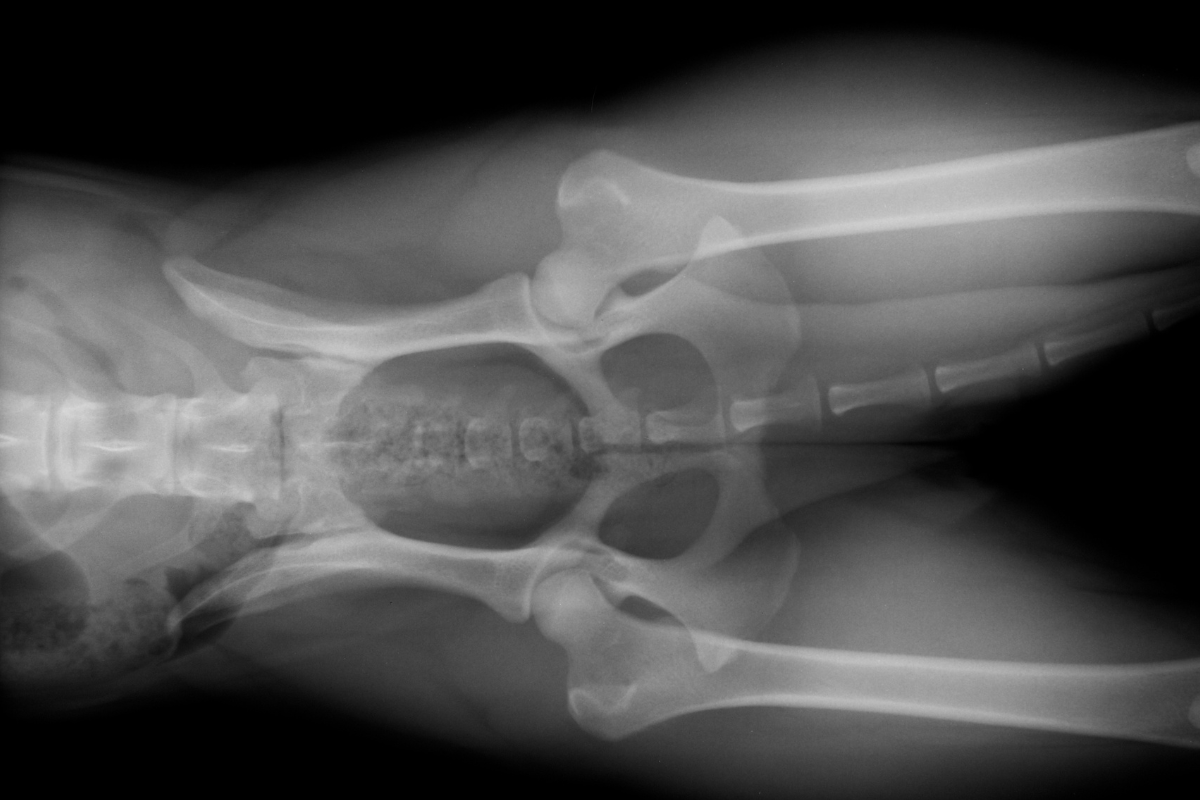

- Radiographies : idéales pour visualiser les os et détecter d’éventuelles fractures ou malformations.

Grâce à ces outils, le vétérinaire peut voir ce qui est caché sous la surface, un peu comme un super-héros avec des rayons X !